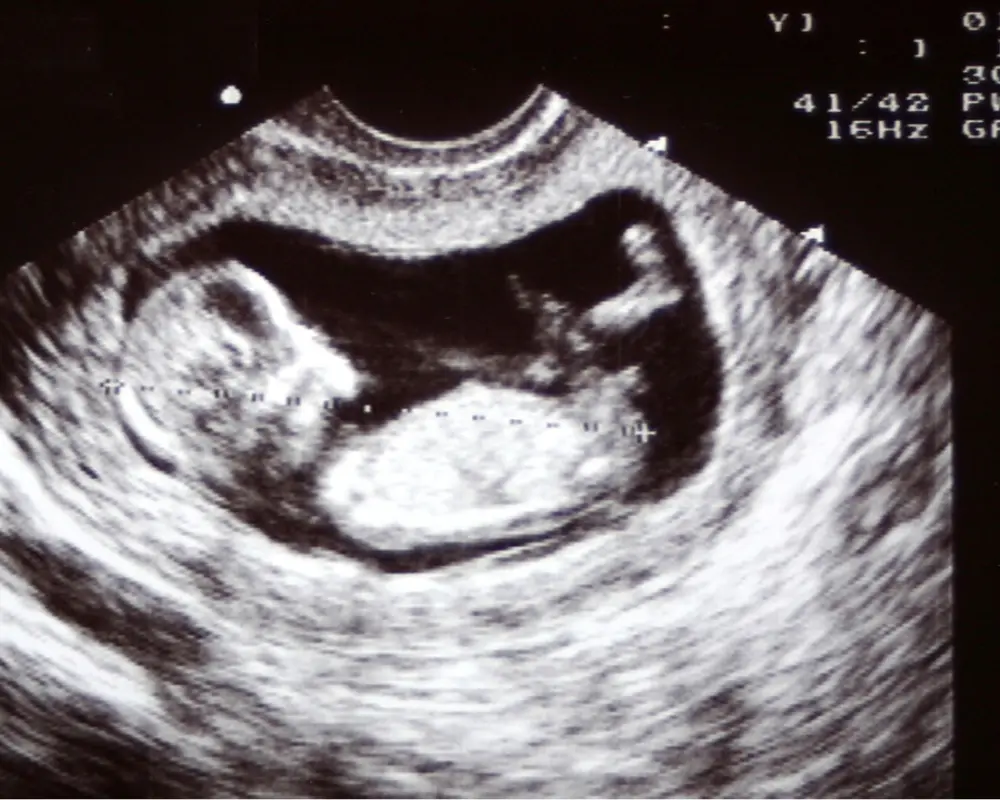

Pregnancy Ultrasound

Pregnancy ultrasound provides detailed imaging to monitor fetal development, confirm pregnancy stages, and ensure both mother and baby are progressing safely throughout each stage.